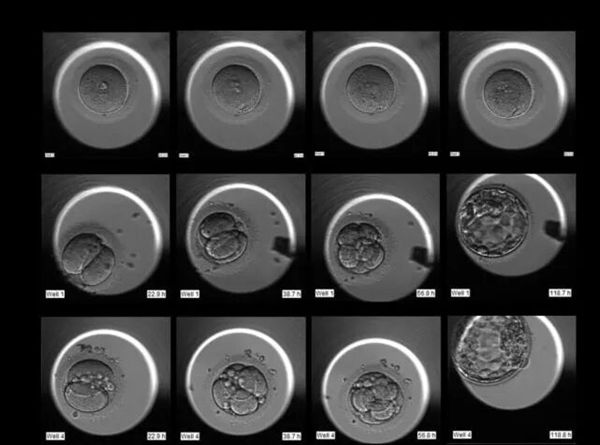

普通选拔:以前是定时拿出来在显微镜下“拍个照”,看谁长得好看(形态好)就选谁。但这样很容易错过细节,有些“照骗”宝宝可能实际发育得并不好。

“天眼”选拔:现在有了时差培养箱的“纪录片”,胚胎学家能看清每个宝宝的全过程。那些分裂节奏好、又稳又快的“学霸”胚胎就会被选中!这就大大提高了选中“真王者”的概率!

通常,我们会把宝宝培养到第5-6天,变成结构更复杂的“囊胚”。能练成“囊胚”的,都是潜力股,移植进妈妈子宫后成功率自然就更高啦!